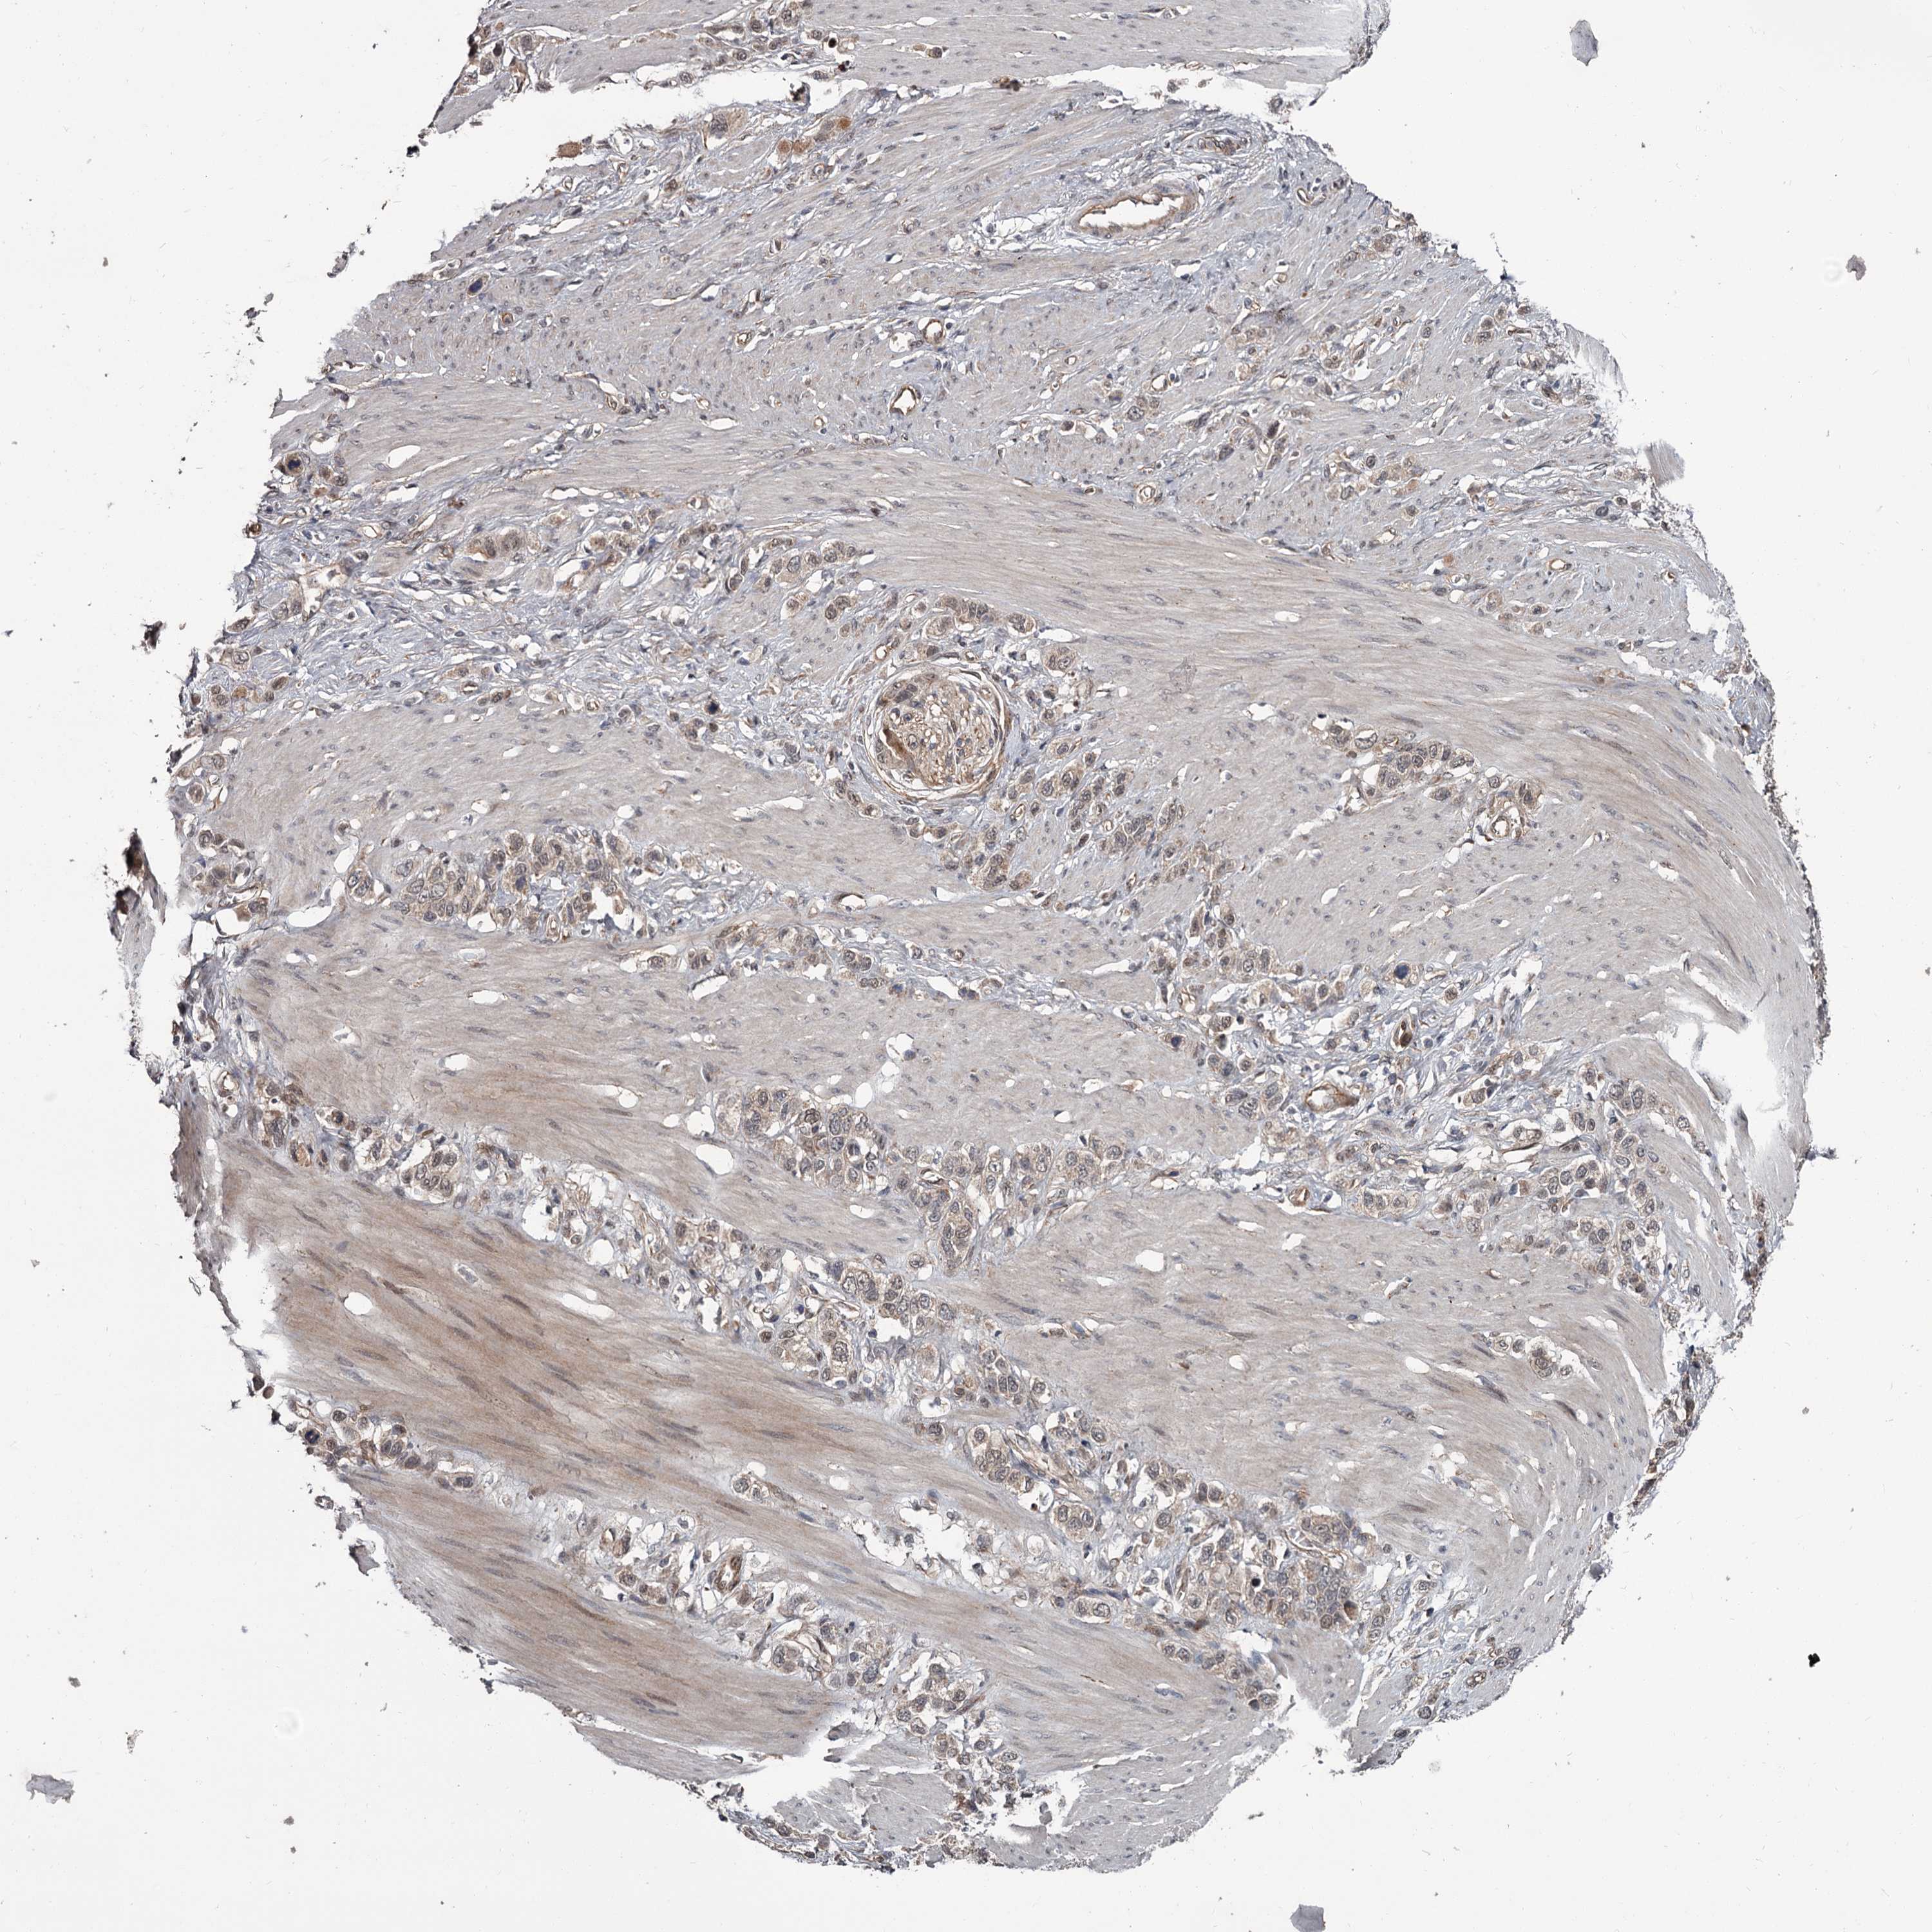

STOMACH CANCER - Protein expressioni

A mouse-over function shows sample information and annotation data. Click on an image to view it in a full screen mode. Samples can be filtered based on level of antibody staining by selecting one or several of the following categories: high, medium, low and not detected. The assay and annotation is described here.

Note that samples used for immunohistochemistry by the Human Protein Atlas do not correspond to samples in the TCGA dataset.

Antibody stainingi

Antibody staining in the annotated cell types in the current human tissue is reported as not detected, low, medium, or high, based on conventional immunohistochemistry profiling in selected tissues. This score is based on the combination of the staining intensity and fraction of stained cells.

Each image is clickable and will lead to virtual microscopy that enables deeper exploration of all samples and also displays staining intensity scores, fraction scores and subcellular localization as well as patient and tissue information for each sample.

Antibody HPA038562

Staining

High

Medium

Low

Not detected

Intensity

Strong

Moderate

Weak

Negative

Quantity

>75%

75%-25%

<25%

None

Location

Nuclear

Cytoplasmic/membranous

Cytoplasmic/membranous,nuclear

Adenocarcinoma, NOS

Adenocarcinoma, High grade